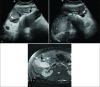

Objective: The objective of the study was to evaluate the safety and efficacy of percutaneous cholecystostomy (PC) in treating critically ill patients with emphysematous cholecystitis who were deemed poor surgical candidates.

Materials and methods: The Institutional Review Board exemption was obtained for this retrospective study. Patients with emphysematous cholecystitis who were deemed to be poor operative candidates by the treating surgeon and underwent PC placement between May 2008 and April 2017 at a single institution were identified through a medical records search. Demographics, laboratory values, imaging data, procedural technique, complications, hospitalization course, clinical outcome, and survival data were obtained.

Results: Ten consecutive patients were included, with a mean age of 75.0 ± 12.2 years, including six men and four women. The most common comorbidity was diabetes (60%, 6/10) followed by hypertension (40%, 4/10). Intraluminal or intramural gas as well as gallbladder wall thickening were noted in all patients. Procedure technical success rate was 100%. There was a complete resolution of symptoms in 90% (9/10) of patients at a mean of 2.9 ± 1.4 days post-procedure. Thirty-day survival rate was 90% (9/10); one patient died on the 6th post- procedure day from sepsis. Two more deaths occurred within a year after PC from unrelated causes. About 50% (5/10) of patients underwent elective cholecystectomy at a median interval of 69 days post-procedure. In 40% (4/10) of patients, cholecystostomy was the definitive treatment, with tube removal at a median of 140 days post- procedure.

Conclusion: PC appears to be a safe and generally effective alternative management option in patients with emphysematous cholecystitis that is considered very high risk for surgery.